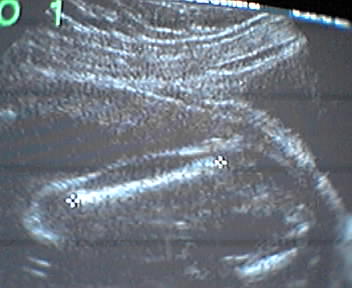

Our third ultrasound today captured our Wascaly Wabbit at 21 weeks. The black and white screen snaps here are of biometric overlays measuring the cranium, femur and heartbeat. Lord, the dotted line around our baby princess girl's head even looks like a crown.

- mike lee - baltimore